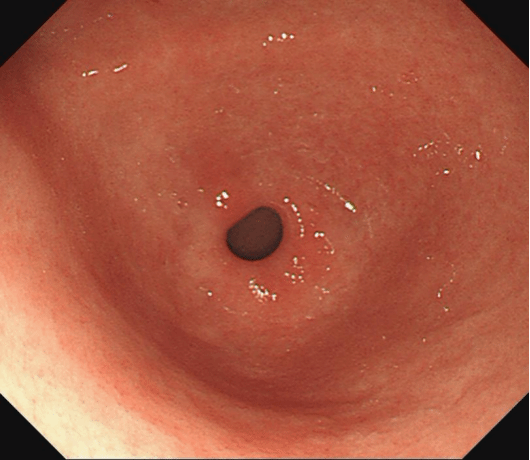

治疗后:黏膜红白相间,以红为主,白相轻凹,散见充血斑。